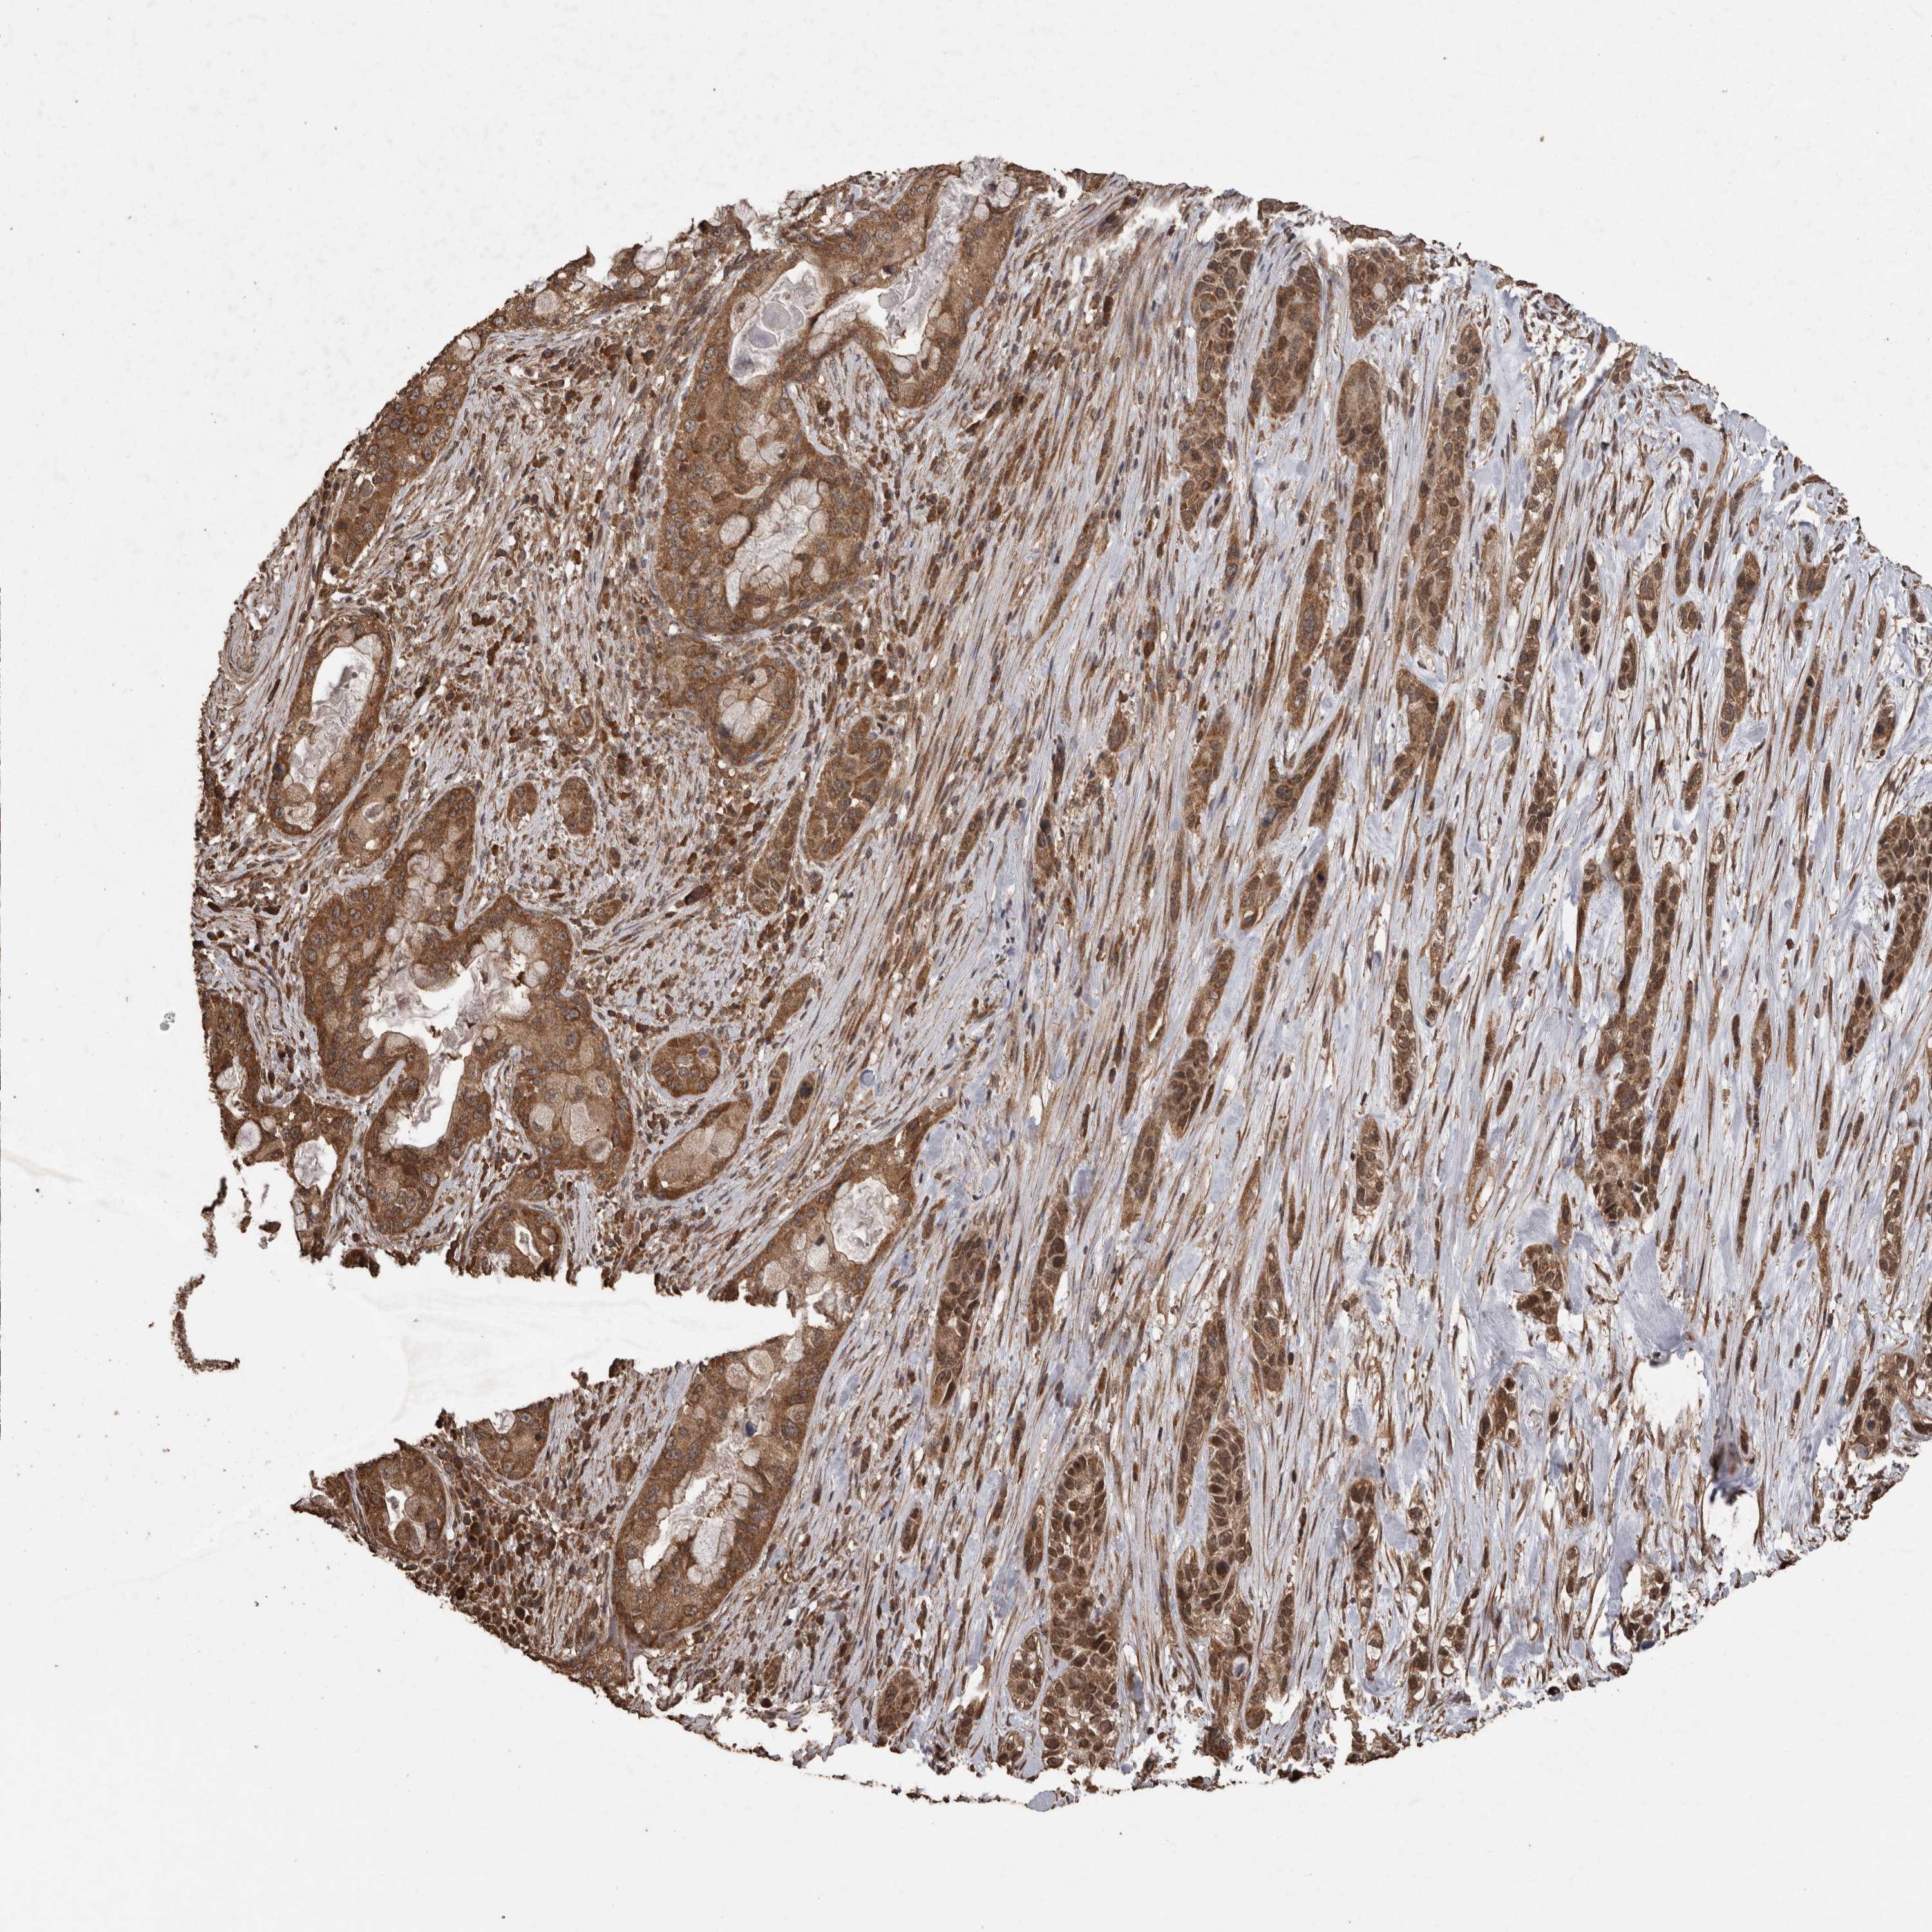

PANCREATIC CANCER - Protein expressioni

A mouse-over function shows sample information and annotation data. Click on an image to view it in a full screen mode. Samples can be filtered based on level of antibody staining by selecting one or several of the following categories: high, medium, low and not detected. The assay and annotation is described here.

Antibody stainingi

Antibody staining in the annotated cell types in the current human tissue is reported as not detected, low, medium, or high, based on conventional immunohistochemistry profiling in selected tissues. This score is based on the combination of the staining intensity and fraction of stained cells.

Each image is clickable and will lead to virtual microscopy that enables deeper exploration of all samples and also displays staining intensity scores, fraction scores and subcellular localization as well as patient and tissue information for each sample.

Antibody HPA001931

Antibody CAB026191

Staining

High

Medium

Low

Not detected

Intensity

Strong

Moderate

Weak

Negative

Quantity

>75%

75%-25%

<25%

None

Location

Nuclear

Cytoplasmic/membranous

Cytoplasmic/membranous,nuclear

Adenocarcinoma, NOS